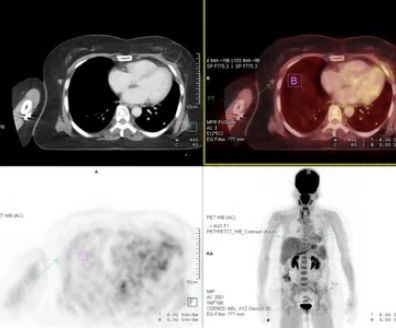

폐암 검사방법

폐암은 전 세계적으로 많은 사람들이 직면하는 심각한 건강 문제 중 하나입니다. 조기 발견과 적절한 진단은 폐암 치료의 성공률을 높이는 데 매우 중요합니다. 이 글에서는 폐암 검사 방법에 대해 자세히 알아보겠습니다.

폐암 검사는 크게 이미지 검사와 조직 검사로 나눌 수 있습니다. 이미지 검사는 폐의 이상 유무를 확인하기 위해 사용되며, 조직 검사는 발견된 이상이 폐암인지를 확진하기 위해 필요합니다.

이미지 검사에는 흉부 X-레이, 컴퓨터 단층촬영(CT), 자기공명영상(MRI) 등이 있습니다. 흉부 X-레이는 가장 기본적인 검사로, 폐의 큰 이상을 찾는 데 도움을 줍니다. CT는 더 자세한 이미지를 제공하여 작은 종양이나 이상을 찾는 데 유용합니다. MRI는 주로 뇌나 척수의 이상을 찾는 데 사용되지만, 특정 상황에서 폐암 진단에도 활용될 수 있습니다.